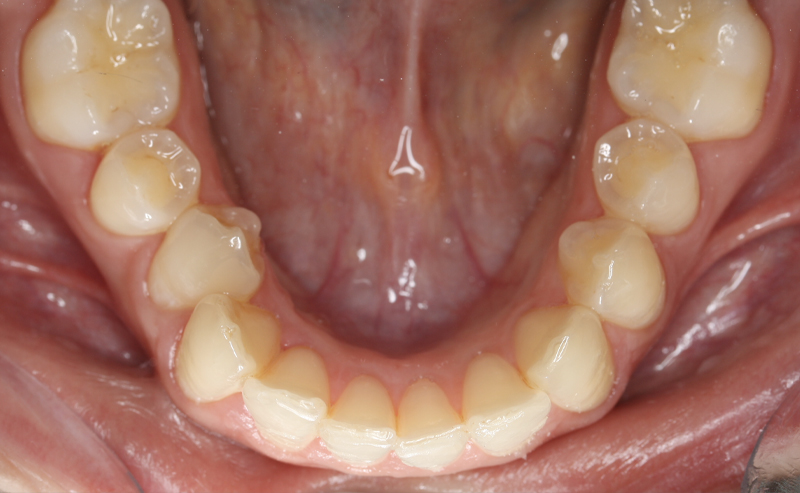

Fotografe a sua Boca de acordo com os exemplos abaixo demonstrados